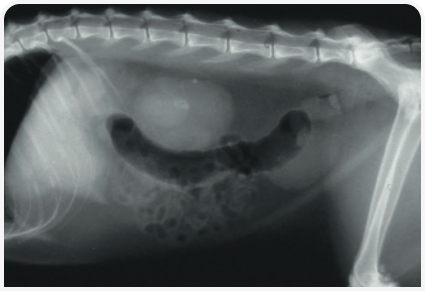

Мочевые камни часто визуализируются на обзорных рентгенограммах, хотя мелкие или рентгенопрозрачные камни, или находящиеся над позвоночником или содержимым толстой кишки камни можно и пропустить; чувствительность обзорной рентгенографии для выявления мочевых камней у кошек составляет около 81% (7). Если во время проведения рентгенографии отделить мочеточник от других органов брюшной полости, сдавив мочевой пузырь (например, деревянной ложкой), это способствует более легкому выявлению мочевого камня.

В некоторых случаях расширение мочеточника может не доходить до степени непроходимости (Рисунок 1). Ультразвуковое исследование также полезно для мониторинга, выявления прогрессирующей дилатации мочеточника и оценки необходимости хирургического вмешательства.